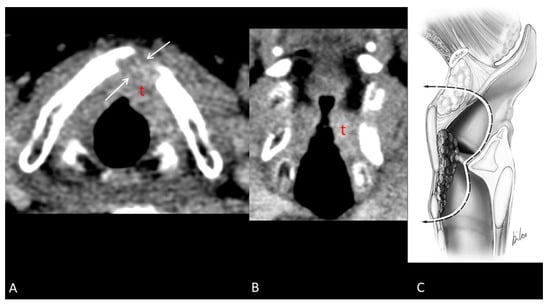

- Maroldi, R.; Ravanelli, M.; Farina, D. Magnetic resonance for laryngeal cancer. Curr. Opin. Otolaryngol. Head Neck Surg. 2014, 22, 131–139. [Google Scholar] [CrossRef]

- Ferreiro-Argüelles, C.; Jiménez-Juan, L.; Martínez-Salazar, J.M.; Cervera-Rodilla, J.L.; Martínez-Pérez, M.M.; Cubero-Carralero, J.; González-Cabestreros, S.; López-Pino, M.A.; Fernández-Gallardo, J.M. CT findings after laryngectomy. Radiographics 2008, 28, 869–882; quiz 914. [Google Scholar] [CrossRef]